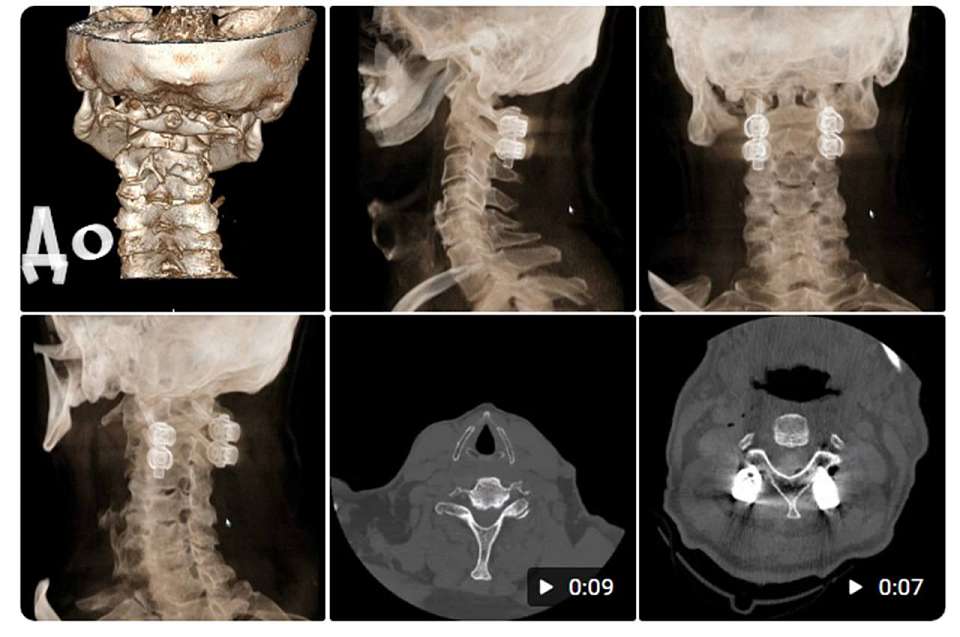

Сразу после их возвращения в отделении оказался пациент с тяжелым переломом тела и дуг позвонка С2 (тип 3 по классификации Андерсона). Такие клинические ситуации требуют проведения сложных операций по методике Хармса, техники которой как раз были изучены в Нижнем Новгороде. Операцию провели врач Павел Юров и его ассистенты Анвер Магомедов и Александр Максимов. В команде также работали анестезиолог Андрей Руденко и операционная медсестра Анна Романова.

Пациент был выписан на четвертые сутки после вмешательства, при этом неврологические нарушения отсутствовали. Предшествующие операции жалобы в виде онемения рук значительно уменьшились в послеоперационный период.